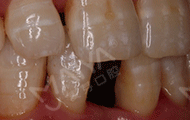

2017年10月28日 当天完成种植手术,非常顺利!

手术当天,我先和在场的朋友们分享了我的缺牙感受,然后进了手术室,除了麻醉的时候有点感觉外,种牙没有一点痛感,自己小咪了几分钟牙就种好了,而且出血量微乎其微,专家们技术真的非常高超。看着镜子里面的牙齿,发现跟周围的真牙完美的融合了,一点也看不出假牙的样子,特别美观舒服。回到现场,大家问我种牙什么感觉,我最想说的就是:种牙真的不疼,而且整个手术时间很快,要相信我们的医生和技术。